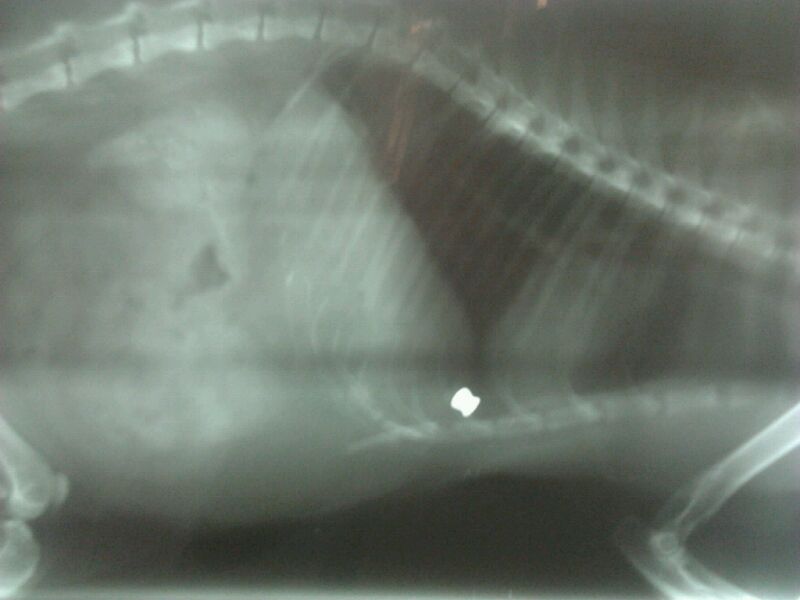

Ahora os adjuntaré las radiografías, para que veáis el balín.

Incluso ha puesto radiografías del balin. Por la penetración en el gato parece una arma potente, además no hay deformación ¿ no ?

Por lo que veo en la foto, su penetración oblicua, el angulo, la deformación o ensanchamiento que se ve en la segunda y sobre todo por el resultado de muerte en el pobre gato me atrevería a asegurar que ha sido producido por una carabina.

La deformacion del balin no es mucha.